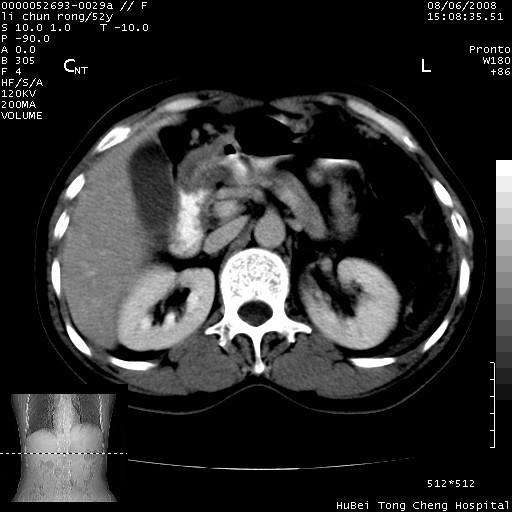

以下是引用云翔在2008-8-7 6:20:00的发言:[br]胰尾部囊性病变,考虑假囊肿,结合实验室检查疾病史

以下是引用zjzjr在2008-8-7 8:38:00的发言:[br]支持胰腺炎伴假囊肿形成,左肾小囊肿.少量腹水.

以下是引用随光逐影在2008-8-7 9:12:00的发言:[br]1)考虑胰腺炎伴假性囊肿形成可能性大;胰腺囊腺瘤待排。2)左肾小囊肿。3)少量腹水。